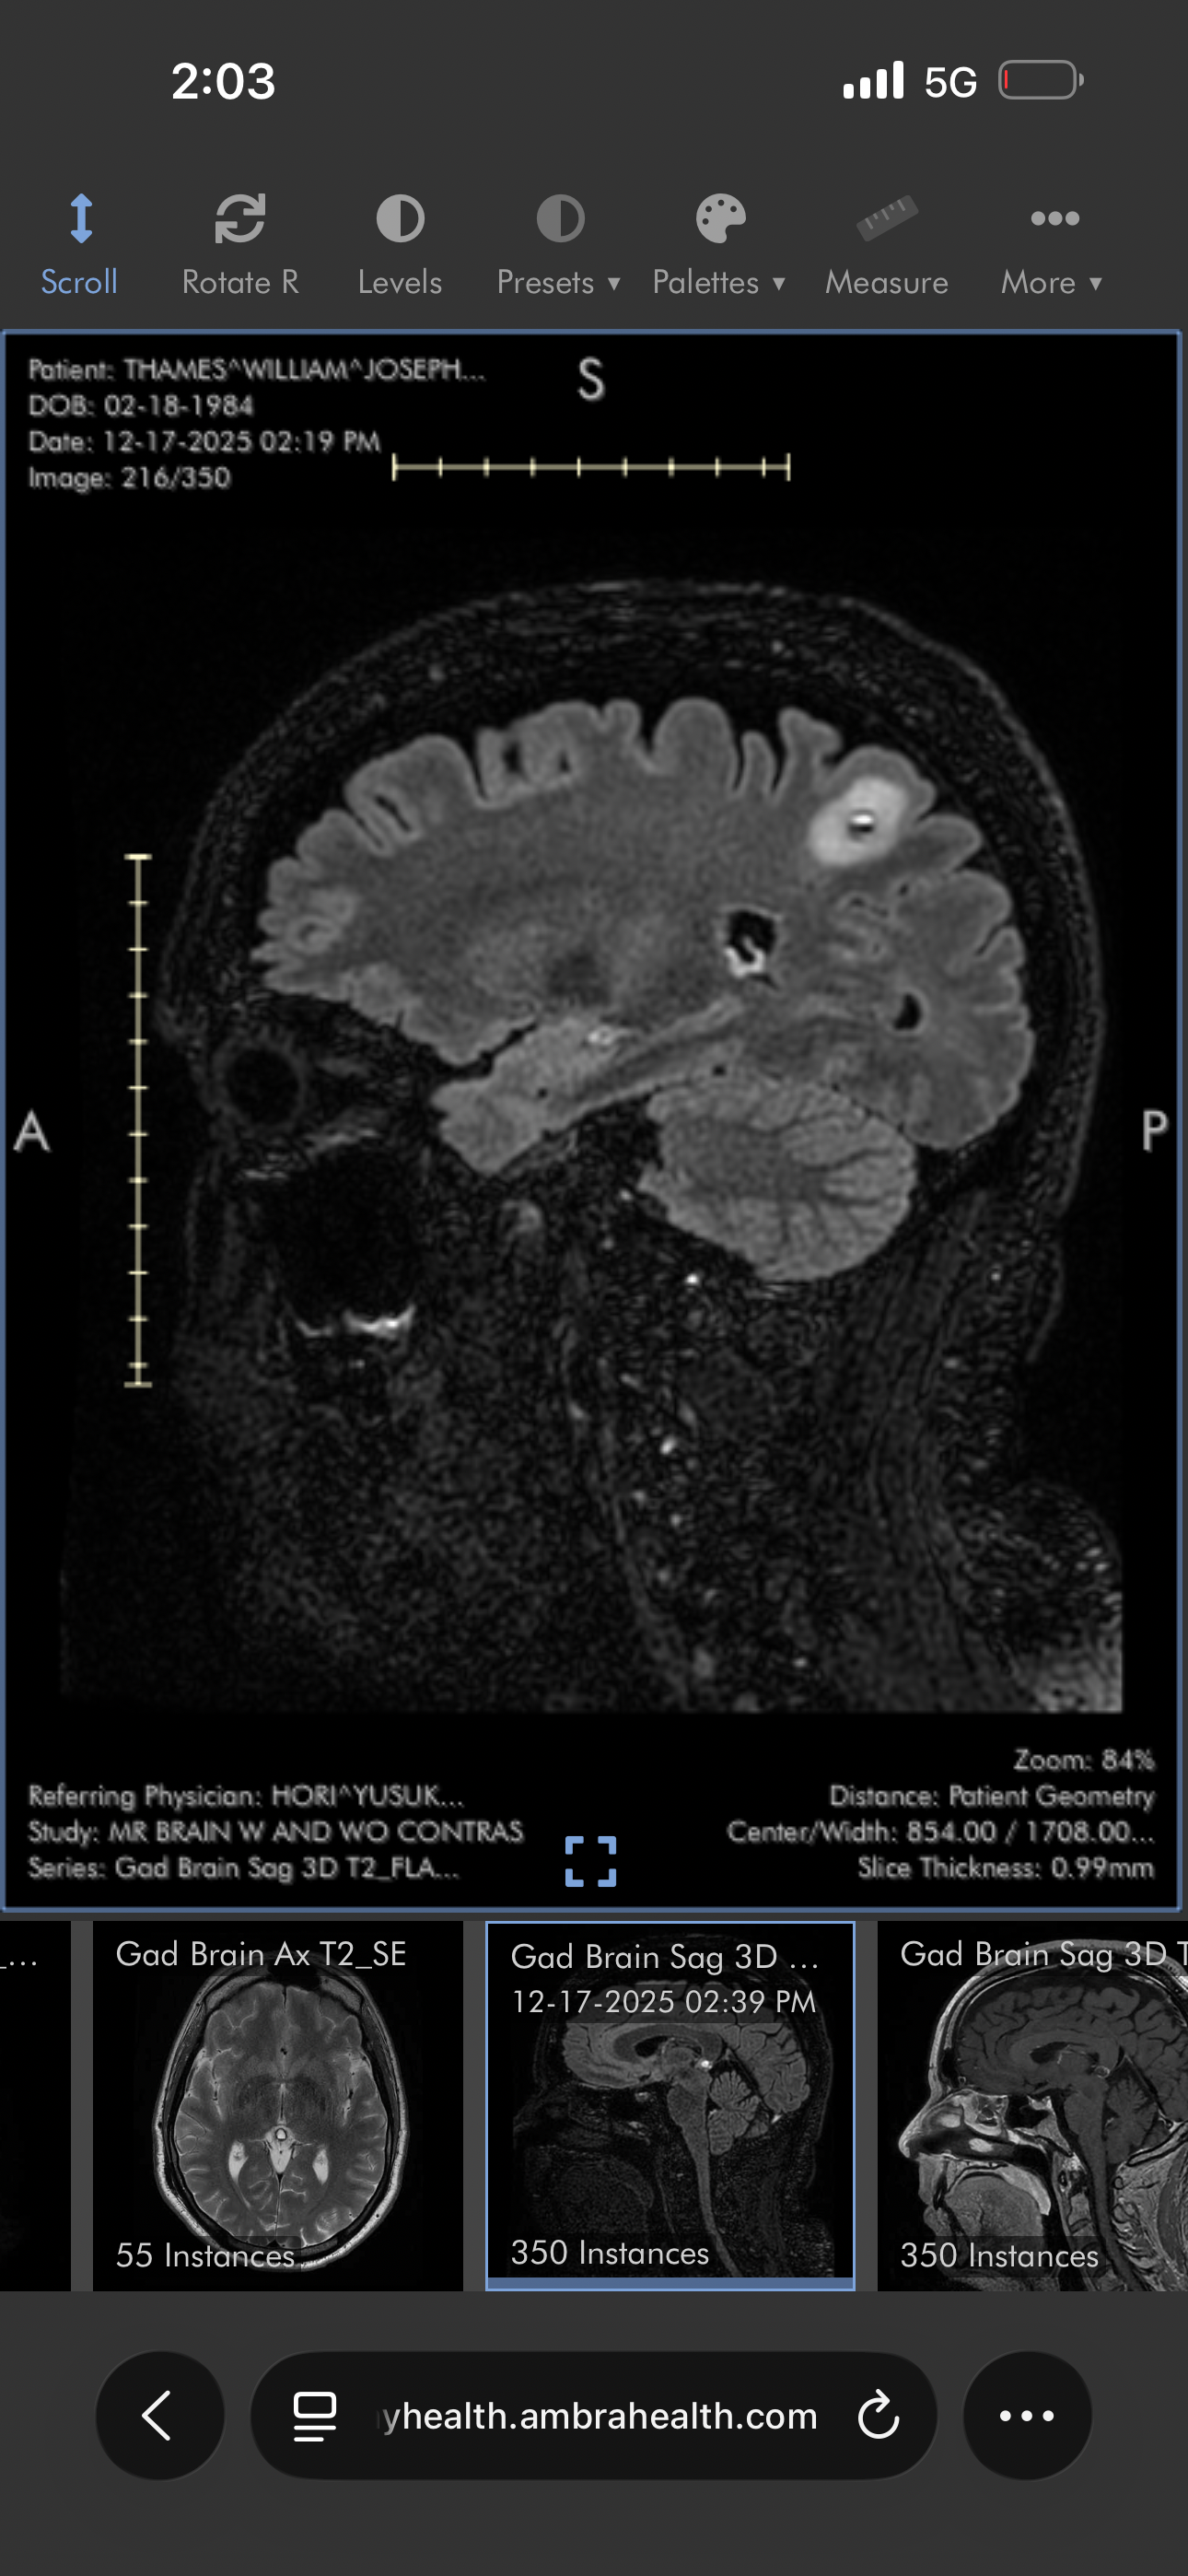

Now, Billy has been diagnosed with Leptomeningeal disease (LMD), a rare and aggressive form of cancer that attacks the membranes around the brain and spinal cord. LMD is unpredictable, relentless, and there are no treatments that can stop it.